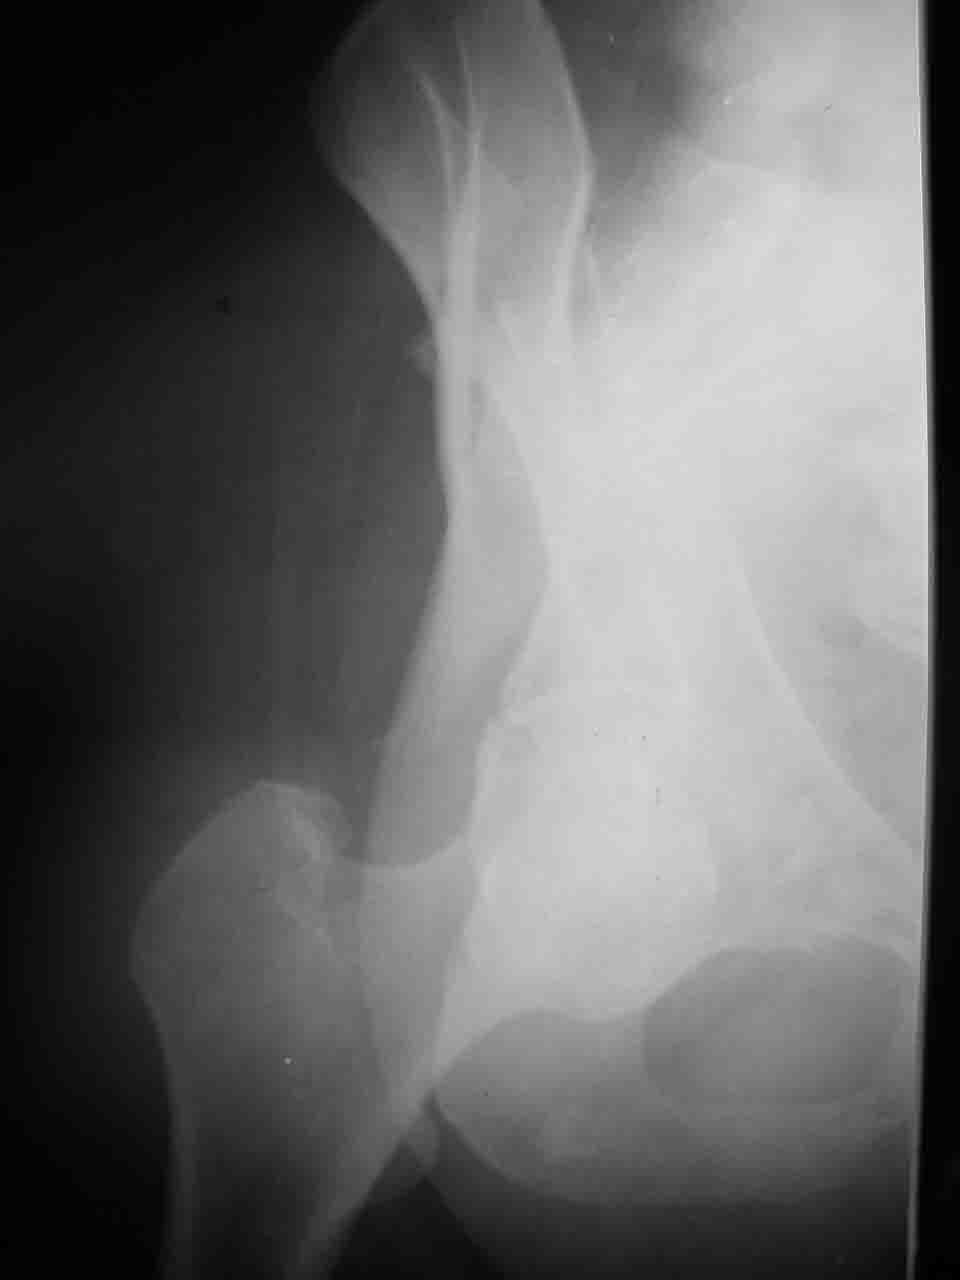

Интерес к реконструкции вертлужной впадины у меня появился довольно-таки давно, но до недавнего времени как-то не ощущалась готовность к практической реализации, а местный подход достаточно консервативен - перелом срастется,

а далее будет видно. Такую точку зрения я не разделяю, поэтому через конференции,ортофорум и свои случаи пытаюсь практически и теоретически *продвинуть* для себя тему реконструкции вертлужной впадины.

Логика подсказывает, что все-таки лучше иметь анатомически полноценную впадину, хотя ранее упоминалось состояние вторичной конгруэнтности и одно наблюдение у меня есть, когда у больного с полностью нарушенной анатомией впадины и подвывихом головки бедра кзади и кверху боли отсутствовали при относительно достаточном для стиля жизни больного объёме движений. Но это только одно наблюдение и кроме перелома впадины у этогобольного была и тяжелая ЧМТ в анамнезе. Основываясь на формулировке структуры ацетабулюм Э. Летурнеля - как перевернутой буквы Y, впадина для полноценной функции сустава должна иметь сферичность, соответствующую размеру головки бедра и если один из компонентов в дефиците, то функциональные последствия рано или поздно проявятся.

Сложностью, ассоциативностью характера перелома, я бы с радостью воспользовался мининвазивной перкутанной фиксацией винтами, но боюсь, что результат был бы ещё хуже, техникой непрямой репозиции перелома не владею, поэтому пытаясь получить анатомичную впадину приходится широко открывать, по крайней мере пока, а дальше буду пытаться уменьшать пространство...

Илеофеморальный доступ не совсем передний и сравнительно с илеоингвинальным, и Кохера-Лангенбека открывает весь наружный таз кроме самых передних отделов лонных костей, фиксацию которых я не ставил в задачу. Обширность диссекции, большая длительность операции и более высокий риск гетерооссификации - отрицательные моменты в обмен на возможность легче ориентироваться.